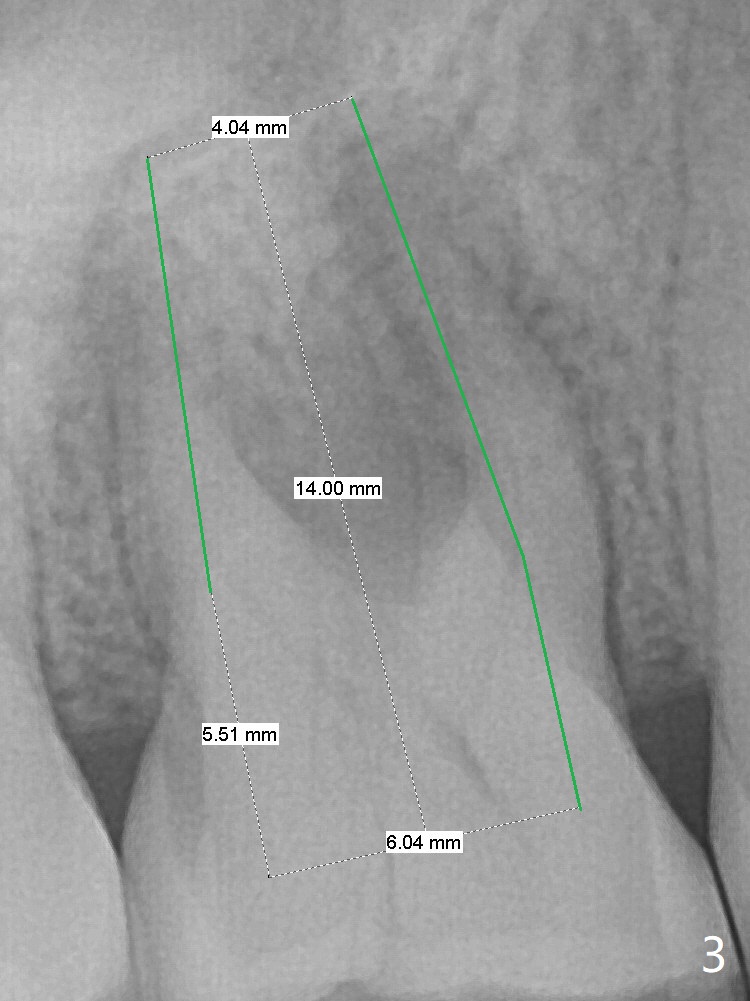

A 53-year-old woman has crack tooth symptom at #3 with apparently a vertical crack line on PA (Fig.1 arrow), suggesting bruxism. The latter may be easily associated with abutment screw loosening. To avoid this complication, a tissue-level implant will be placed (Fig.3). After extraction, the initial depth of osteotomy in the septum will be 7 mm (Fig.2). Find a pointed drill. Take preop photos to show the possible buccal crack line.